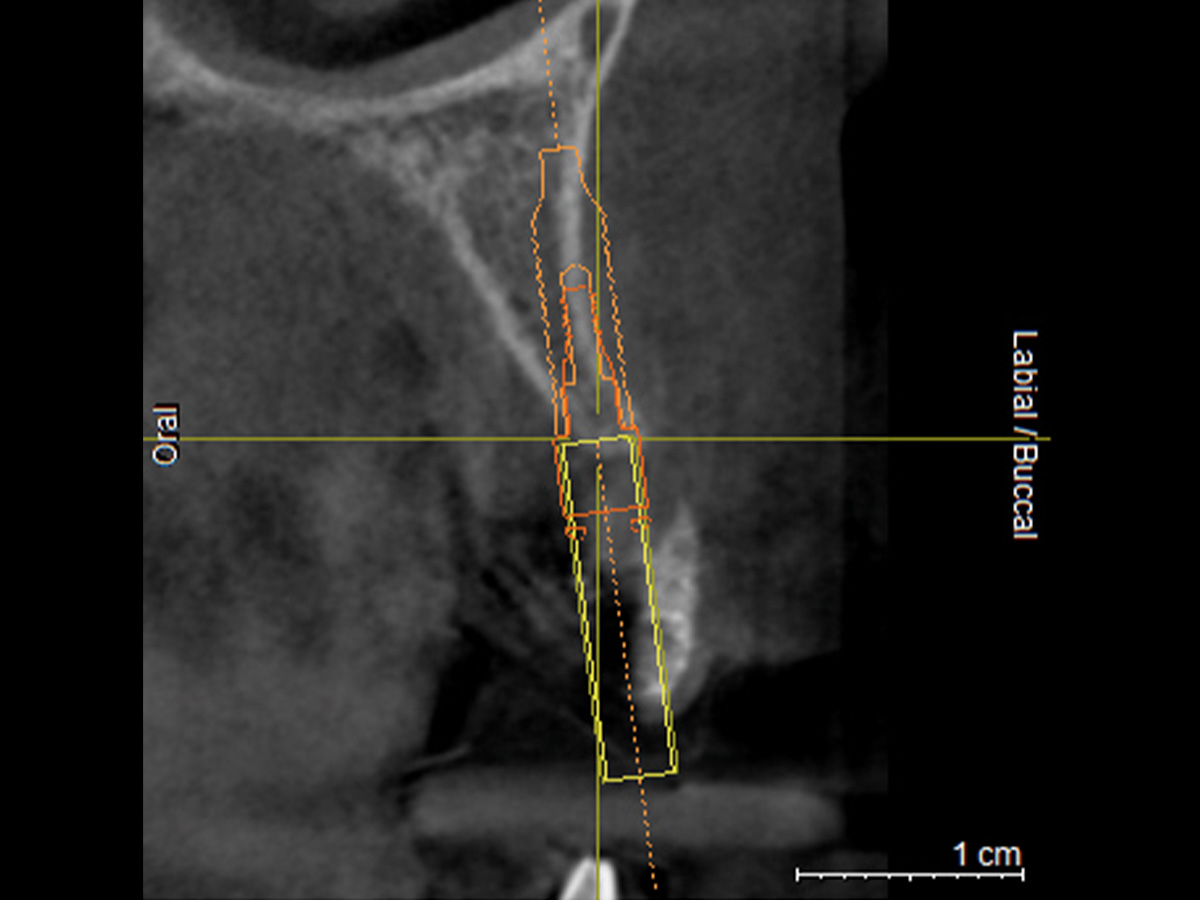

In diesem Fall war bereits aus der präoperativen DVT-Planung ersichtlich, dass die vorhandene Breite des Alveolarkammes zu schmal ist, um ein Implantat mit der Breite 3,25/3,4 Biomet 3i aufzunehmen. Intraoperativ wurde das Implantat so gesetzt, dass es koronal zwar mit einer ca. 2-3 mm breiten Knochenmanschette ummantelt war, der Rest der Implantatzirkumferenz aber außerhalb des Alveolarkammes zu liegen kam. Nach Anfrischung des periimplantären kortikalen Knochenbettes mit Rosenbohrern wurde eine Bone Lamina angepasst und mit zwei Frioss-Nägeln stabilisiert. Der dadurch entstandene Hohlraum wurde mit mp3 aufgefüllt. 5 Monate postoperativ wurde das Implantat freigelegt und die bukkale Knochenbildung dargestellt.

Abbildung 2

DVT mit Implantatplanung zeigt die atrophe Knochensituation mit geplantem Implantat.

Abbildung 3

3D-Darstellung der geplanten Implantatposition.